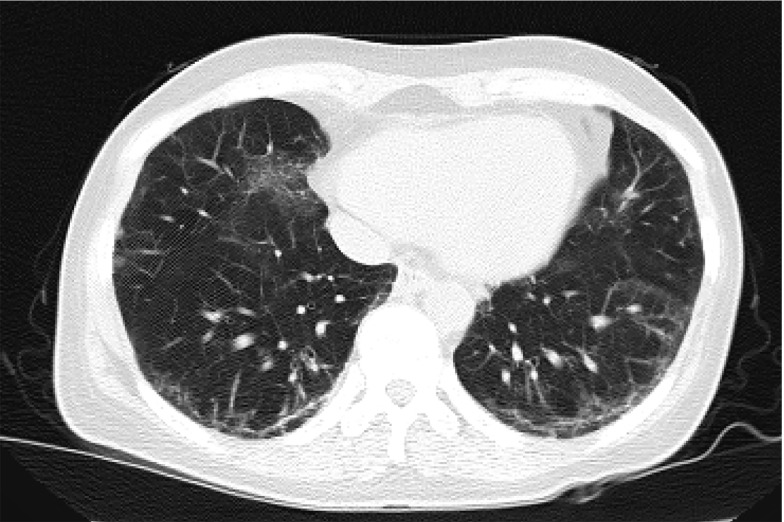

Case presentation: We report the successful use of spinal anesthesia (SA), ESPB, and magnesium sulfate in a high-risk patient with systemic sclerosis and pulmonary fibrosis undergoing laminectomy. A multimodal approach was selected due to the patient's underlying condition. This strategy minimized respiratory complications associated with general anesthesia while providing effective surgical anesthesia and postoperative pain control without opioid-related complications.